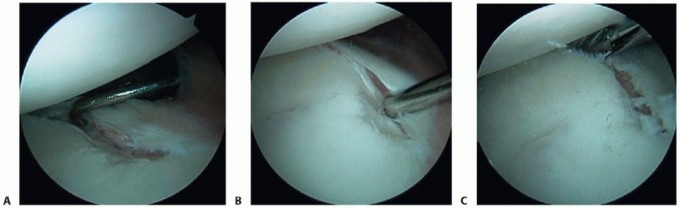

Repair is begun by assessing the posterior labral construct for the presence of labral displacement and tearing (TECH FIG 1A).

A grasper is used to capture the posterior band of the inferior glenohumeral ligament (IGHL), attempting to mobilize it superiorly to determine the amount of capsular laxity and ultimate position for repair.

If a posterior Bankart lesion is identified, a Liberator knife (ConMed Linvatec) is used to mobilize the labrum (TECH FIG 1B), and a burr is used to débride the posterior face of the glenoid in preparation for anchor placement (TECH FIG 1C).

This is a critical step so that a freely mobile labrum can be placed up on the glenoid, thereby restoring its bumper effect. Anchor placement begins at the most inferior aspect of the glenoid, usually the 5:30 or 6:30 position, depending on the side involved (TECH FIG 1D).

TECH FIG 1 • A. Probe entering the posterior cannula is demonstrating mobility of posterior Bankart lesion with evidence of granulation tissue in the defect. B. After the lesion is defined, a Liberator knife is introduced to take down the fibrous interface in the posterior Bankart lesion. C. After preparation using a high-speed burr, the posterior inferior aspect of the glenoid is lightly decorticated in preparation for anchor placement. D. Initial anchor placement begins at the inferior extent of the glenoid with the use of a guide. E. First anchor in place 2 mm up on the articular surface.

This position allows secure placement of an anchor while allowing optimal inferior capsular plication. Bioabsorbable anchors are employed for this reconstruction (TECH FIG 1E).